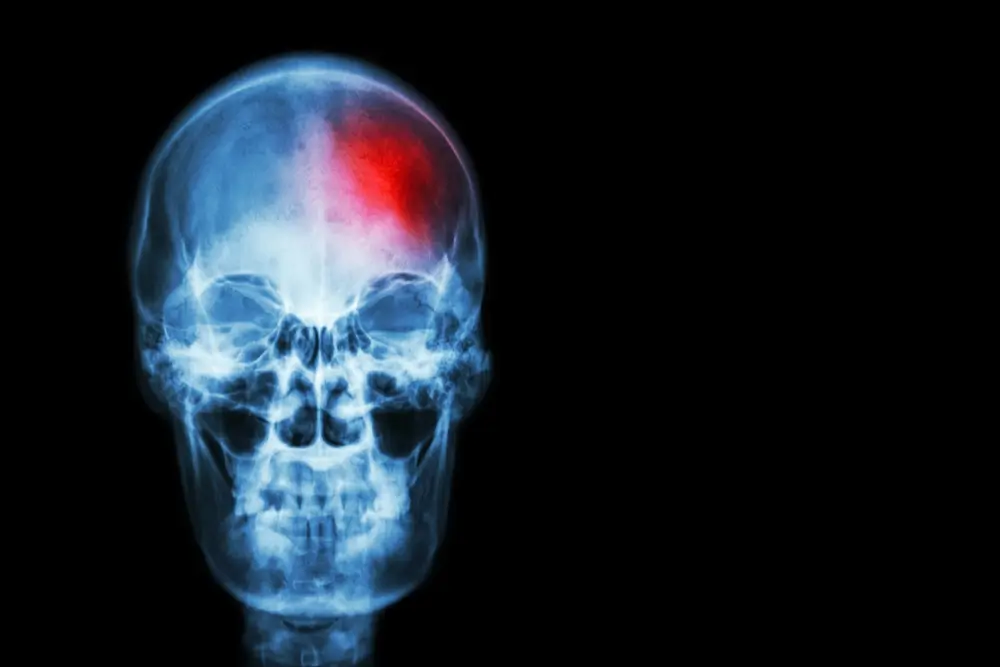

- A stroke is when the blood supply to a part of the brain is cut off.

- The area of brain tissue supplied by that blood vessel can no longer get oxygen and other vital nutrients, and starts to die.

- If the blockage is not removed quickly, the damage can be permanent.